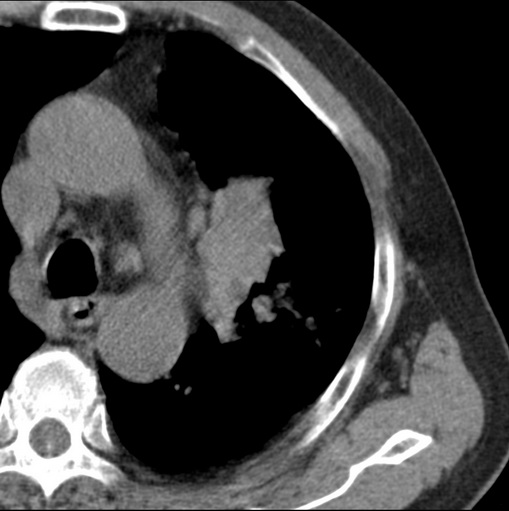

标题: CT25434:胸部CT增强扫描

男性患者 81岁 咳嗽 咳痰 咯血

肿块贴近左肺门,包绕左上肺动脉,形态不规则。肿块增强扫描中度强化。纵膈内主动脉弓左旁间隙、气管隆突前、下间隙见多枚淋巴结影。综上考虑左侧中央型肺癌可能性大。图片没有完整上传,尤其是左肺上叶支气管分支层面没有上传,因此不好判断是叶支气管中断还是段支气管中断。另外,下图红色部分所示是“黏液支气管征”吗?